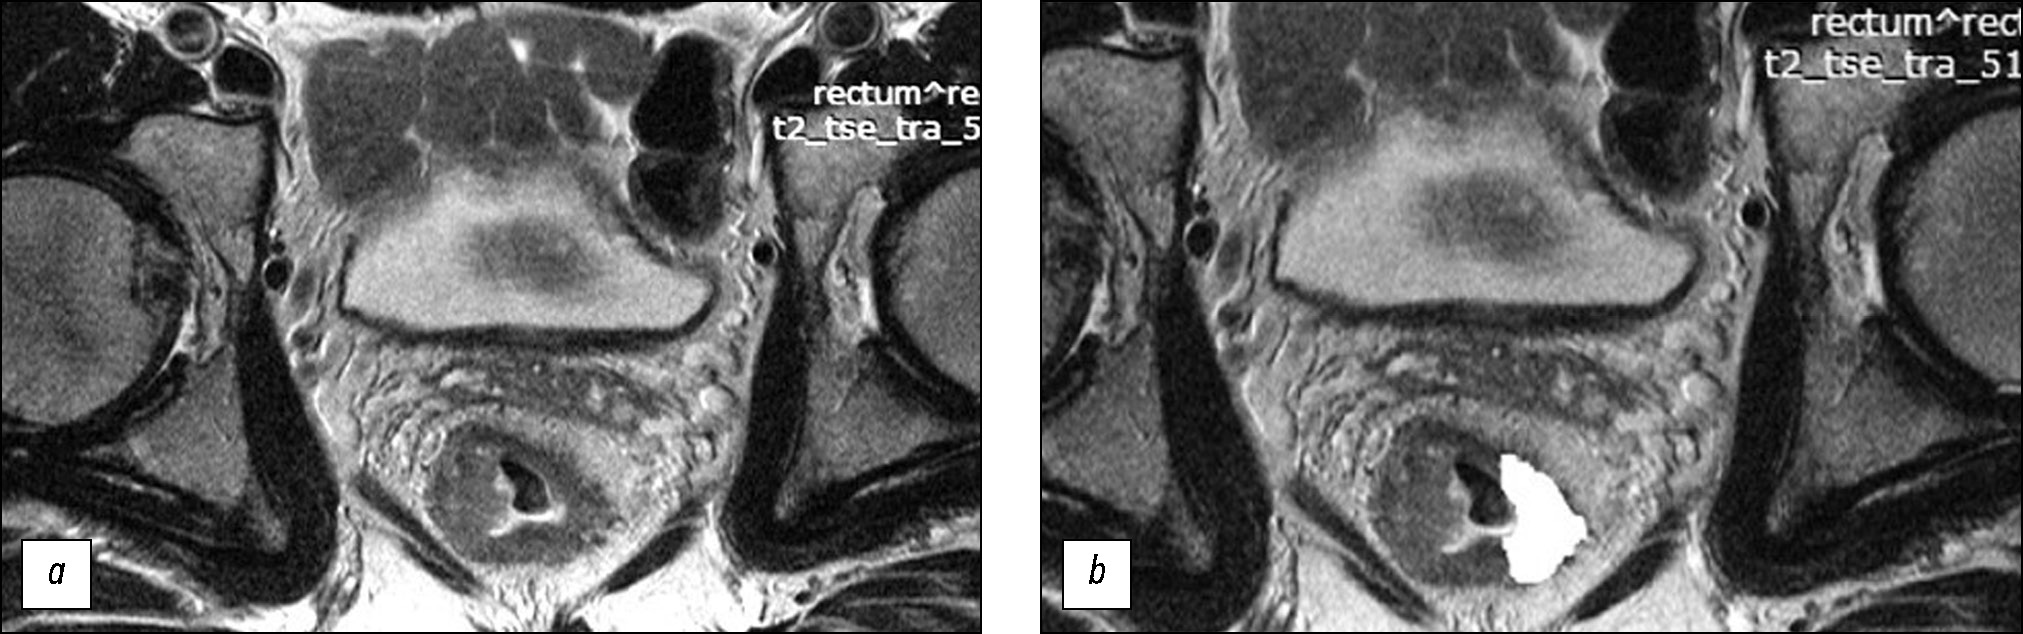

基于直肠癌患者初诊分期时获得的肿瘤加权T2核磁共振图像的纹理分析预测新辅助放化疗的效果

研究目的 — 评估局部晚期直肠癌在原发加权T2图像上的纹理特征,将其作为预测标准新辅助放化疗效果的潜在因素,并在此基础上开发一套预测此类治疗效果的系统。

材料和方法。在回顾性研究中接受新辅助放化疗综合治疗的局部晚期直肠癌患者(n=82)被分为训练样本(n=58)和对照样本(n=24)。在肿瘤中心水平使用方向垂直于肠壁的高分辨率原始加权T2图像,用于纹理分析。纹理分析基于灰度级共生矩阵(GLCM),借助MAZDAver计算机程序执行了二阶统计法。 4.6和11个纹理参数的计算。在训练样本中进行手术制剂形态学评估后,查明治疗有反应(预后良好组)和无反应(预后不良组)患者组的纹理分析参数的真实差异,并在此基础上创建评估新辅助放化疗效果的评分系统。系统在对照样本上进行测试确定诊断效率的参数。

结果。在训练样本的预后良好组和预后不良组中找到分离点,其五个纹理参数上存在真实差异:AngScMom(p=0.021)、SumofSqs(p=0.003)、SumEntrp(p=0.003)、Entropy(p=0.038)和 SumVarnc(p=0.015),在创建评分系统时排除了 Entropy,因其与 SumEntrp相比有很强的直接相关性,最低的AUC, 以及与SumofSqs相比重现性低。反应预测评分系统的诊断效率在训练样本中的灵敏度、特异性、阳性预测能力和阴性预测能力分别为 72%、69%、70% 和 71%,相应的在对照样本中分别为 80%、64%、62% 和 82%。曲线下面积在训练样本中为 ROC 为 0.77,在对照样本中为 0.72。

结论。对局部晚期直肠癌患者原发肿瘤T2-VI的纹理分析可以预测诊断效率适中的新辅助放化疗效果,表明这个方向的进一步研究的前景性。